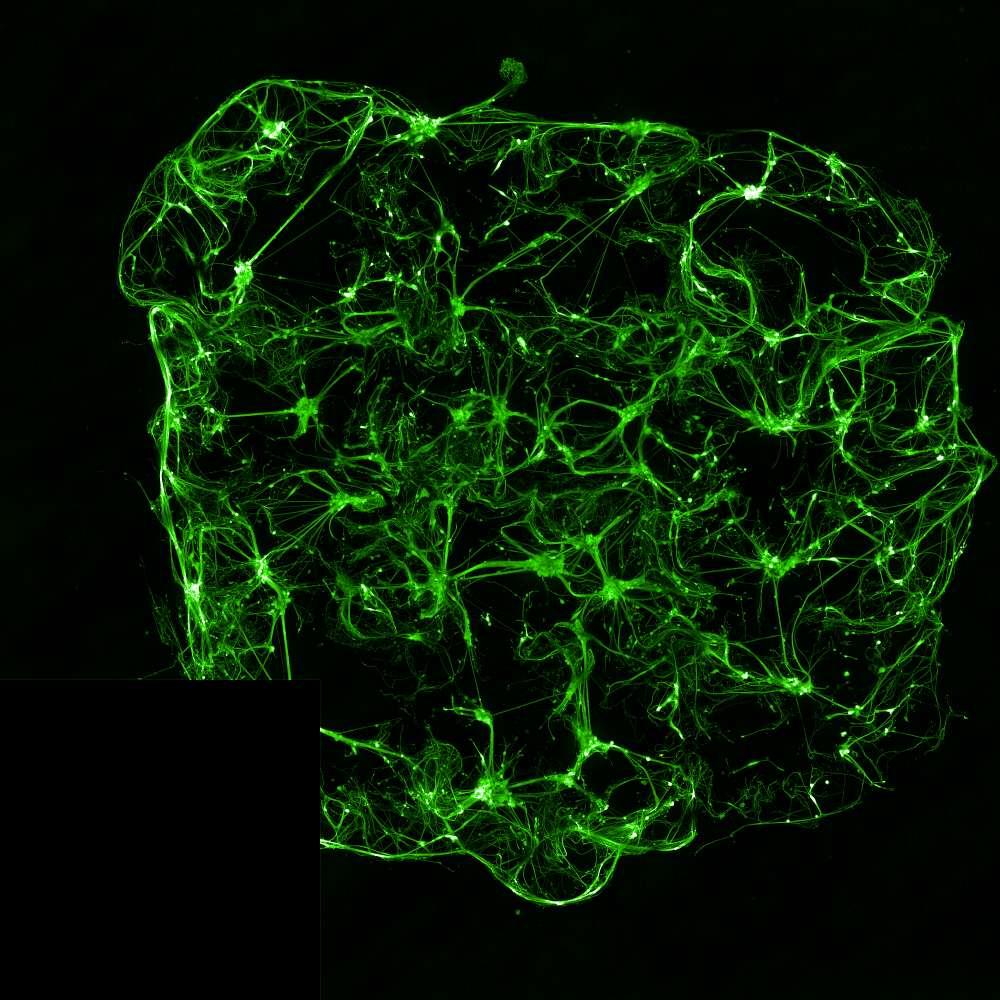

Projection of neurites through microchannels at 2 weeks

• Isogenic control or SNCA A53T mutation neurons were plated in both chambers of a microfluidics device then cultured to allow the neurons to connect via the microchannels

• PFFs were added to the donor chamber only before fixing and labelling for pS129 α-synuclein

• pS129 positive neurons were detected in donor chambers due to directly applied PFFs and acceptor chambers due to seeded PFFs, though automated analysis failed to detect the small proportion of positive wildtype neurons in acceptor chambers

• A53T mutation increases pS129 pathology in both donor and acceptor chambers